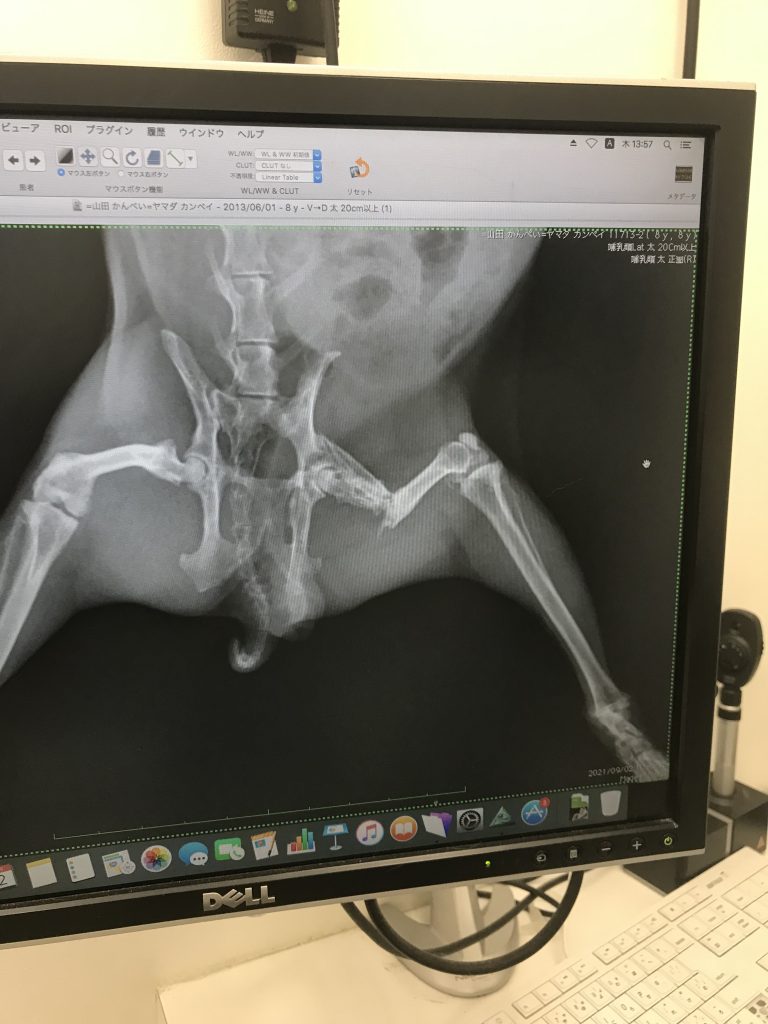

骨折の定期検診に!!!

折れた所はくっつく事なく何となく周りの骨に癒着的にくっついてて、ずっと気になってた折れて尖ったとこは何となぁく尖りがなくなってた!

今のかんぺいのレントゲン写真。